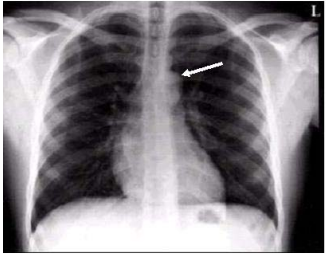

8. 下圖為一正常男性胸部X光的PA片,圖中箭頭所指結構為:

(A)脊椎骨棘突(spinous process) (B)主動脈弓 (C)肺動脈 (D)肺靜脈